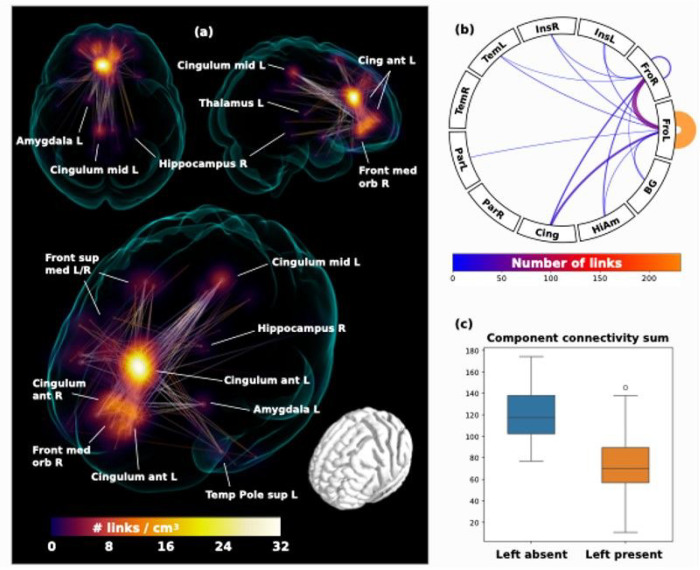

In the second step, the whole brain functional connectome was limited to the identified regions connecting strongly to the ROIs and entered into a network based statistic component calculation (ref. Zalesky, Fornito et al. 2010) comprising a connected set of links on which connectivity differed in accordance with ipsilateral hemispheric PCS presence, based on a binarized connectivity graph at a threshold of P < 0.001 (given group sizes), controlled for the effects of age, sex and handedness. Results of significant network components with altered connectivity and summarizing connectograms are displayed in Figure 4.

Voxel-based Functional connectivity

Two individuals were excluded from analysis as they did not have available handedness data. Voxel based functional connectivity analyses were performed for 127 individuals. The only significant component was identified in individuals possessing a left PCS relative to individuals with an absent left PCS at P = 0.01, controlling for family wise error rate. Results are displayed in Fig. 4. The greatest link density was found converging on the left anterior cingulum, extending inferiorly towards the frontal medial orbitus and the right anterior cingulum. More extended connections were also found to the frontal superior medial gyrus, the left and right posterior cingulum, as well as scattered connections to subcortical structures including the left amygdala, the right posterior hippocampus, and left thalamus.

Voxel-based functional connectivity

We identify that the medial frontal lobe ROI corresponding with the location of the PCS is highly connected to regions of the cingulum, insula, frontal, temporal, and parietal cortex as well as the thalamus, caudate, pallidum, putamen, hippocampus, and amygdala, key components of the DMN and SN, in accordance with standard literature (ref. Catani and Thiebaut de Schotten 2012). In the left hemisphere large-scale connectivity changes were observed revealing a significant network component with greater rsFC in individuals with an absent left PCS relative to those with a present left PCS. This component comprised the left and right anterior cingulum and frontal medial orbitus with more extended connections to the left and right frontal superior medial gyrus and the posterior cingulum, as well as scattered connections to subcortical structures; the left amygdala, the right posterior hippocampus, and left thalamus. The increase in connectivity identifies alternate functional architecture in individuals with an absent left PCS, where distributed network nodes are enlisted creating an alternate specialisation profile with auxiliary processing power drawn from more distal regions outside of the anterior cingulate. Again, with consideration of the findings from the tract segmentation analyses a more dispersed network as identified in individuals with an absent PCS, may become operational where a highly localised network (presumed to exist where a PCS is present) is not present. In turn, cognitive advantages reported in the literature (ref. Fornito, Yücel et al. 2004, Whittle, Allen et al. 2009, Borst, Cachia et al. 2014, ref. Cachia, Del Maschio et al. 2017) associated with the presence of a left PCS may be underpinned by an efficient highly localised network dependent on U-fibres rather than a well organised cingulum bundle. These observations are in line with and provide further evidence for the tension-based morphogenesis theory of cortical folding (ref. Van Essen 1997) and support the notion that well interconnected brain regions display strong patterns of functional connectivity (ref. Segall, Allen et al. 2012) (ref. van den Heuvel, Stam et al. 2009). Extending this concept to disease, we speculate that a highly connected localised network existing in the presence of a PCS may account for the resilience to disease expression observed in individuals with a right PCS in bvFTD and explain why absence of a left PCS, a neurodevelopmental aberration, has been associated with schizophrenia and OCD (Harper, Lindberg et al. 2022) (ref. Amiez, Neveu et al. 2013, ref. Harper, de Boer et al. 2023) (ref. Yücel, Stuart et al. 2002) (ref. Shim, Jung et al. 2009). Studies exploring these hypotheses in these disease groups are indicated in order to provide evidence for this theory. Furthermore, it is known that AC gyral variability affects gyral volume and thus should be taken into account in the study of relevant diseases (ref. Fornito, Whittle et al. 2006). Here we demonstrate that this is also the case for structural anatomy.